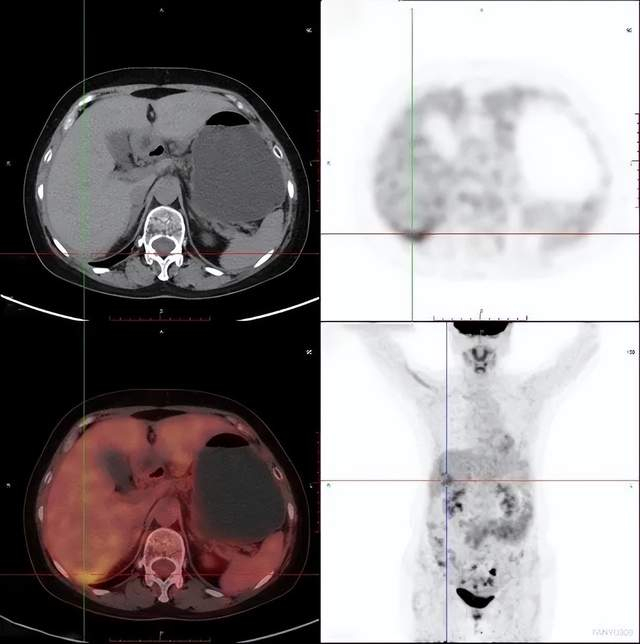

病例3

可疑肝转移患者PET/CT发现原发灶

男性,78岁

相关病史:一直觉得腹部疼痛,在基层医院CT检查,发现肝脏多发低密度灶,怀疑为肝脏多发转移。之后患者在平安健康(检测)中心接受PET/CT检查。

PET/CT影像学表现

上图为肝脏的横断位、冠状位及矢状位图像,依次为PET图像、CT图像、融合图像。图示肝脏体积稍增大,肝内弥漫分布大小不等类圆形低密度灶,部分相互融合,边界不清 ,相应部位放射性摄取明显增高,SUV最大值8.50。

上图显示横断位示胃充盈佳,胃体小弯侧增厚,相应部位放射性摄取异常增高,SUV最大值6.29。

上图中冠矢状位也清楚地显示胃体小弯侧的增厚及FDG代谢的增高。

PET/CT找出原发灶

最后PET/CT诊断为胃癌伴肝脏多发转移,给临床指明了方向,可以制定更针对性的治疗方案。